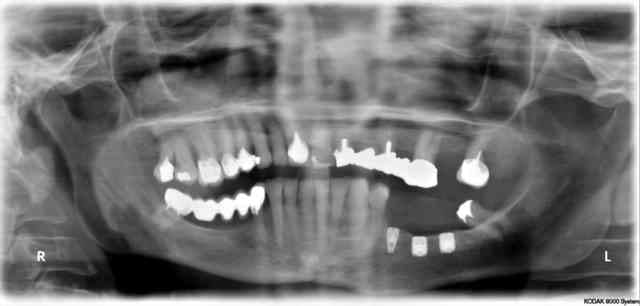

voila la pano

Baby nlfkb5 - Eugenol

Wow, bizare ta pano...le plan d'occlusion...

Ils sont bien petits tes implants...

5 X 6 ?

déformation de la pano...mauvais positionnement du patient (nuque pas assez "tendue")

çà va être chaud pour la prothèse....sacré rapport couronne/implant loin d'être favorable....

rapport couronne racine est de 2

les implants sont 5 *6 et 4*8

il y a effectivement deformation de la pano